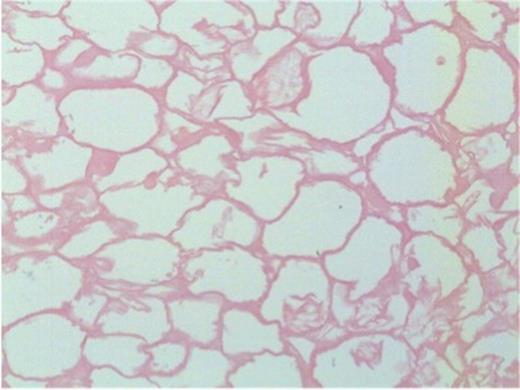

Microscopically, both nodules showed similar histological features. The larger nodule required prolonged, gentle decalcification before reasonable tissue sections could be obtained. Each had a thick shell of dense paucicellular collagen arranged as concentric layers with only a few fibroblasts and inflammatory cells present peripherally (Figures 4b and 5). The shell was devoid of cartilage and it encased necrotic adipose tissue (Figure 6) in which there was focal dystrophic calcification. No granulomatous inflammation, lung parenchyma, abscess formation, caseous type necrosis or neoplasm was identified.

Thick shell of paucicellular collagen surrounding necrotic fat (40x magnification). Inset: Closer view of concentrically arranged thin layers of collagen

Necrotic adipose tissue centrally within the nodule (200x magnification)